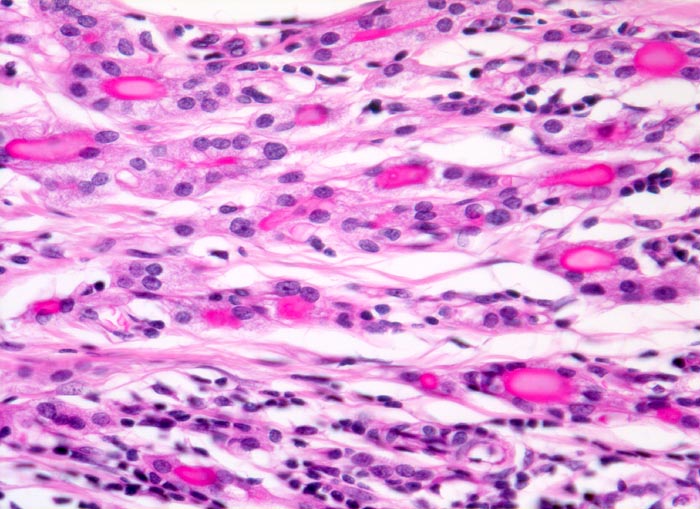

gutartiges reifes Teratom: Schilddrüsengewebe

Kleine Schilddrüsenfollikel enthalten dunkelrotes Kolloid.

Reife Teratome, welche praktisch ausschliesslich aus Schilddrüsengewebe bestehen bezeichnet man als Struma ovarii. Innerhalb dieser Struma ovarii kann sich ausserdem ein strumales Karzinoid entwickeln.